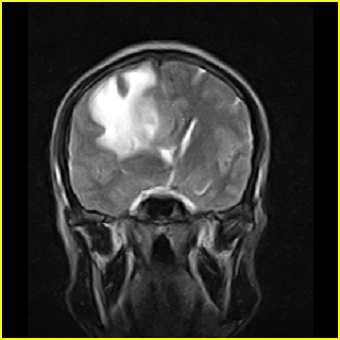

男,45岁,头部剧烈疼痛伴呕吐5天。

右侧额叶见较大的类圆形长t1信号环绕等t1环影,长t2信号环绕短等t2环,周围见明显水肿占位征,中线结构左移,男,45岁,头部剧烈疼痛伴呕吐5天。

右侧额叶,见一占位病灶,t1像病灶、水肿长t1;其间为短t1环行信号。t2像病灶、水肿长t2,其间为短t2环行信号。占位效应明显,中线左移,右测脑室受压闭塞。结合患者发病较急。首先考虑:右侧额叶脑脓肿形成。鉴别:1、转移瘤,多发多见2、胶质瘤。建议增强

t1加权肿瘤呈低信号,肿瘤壁呈等信号.t2 加权时肿瘤呈高信号,肿瘤壁呈等信号.

考虑1脑脓肿.2恶性胶质瘤.